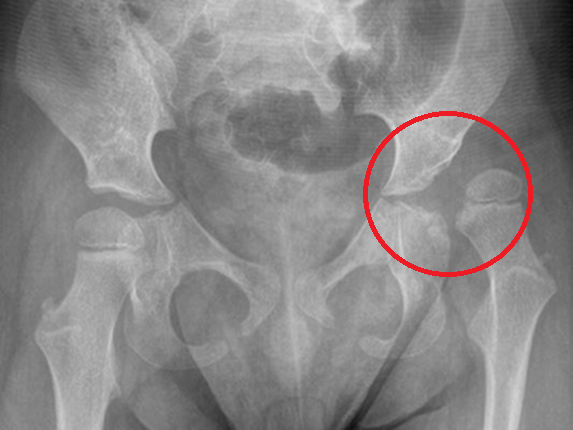

Orthopaedic Complications

Up to 30% of children with long-term neurological conditions, such as dystonia, are complicated by significant functional musculoskeletal impairment. These can manifest as hip subluxation (partial dislocation) or dislocation, scoliosis (twisting of the spine), and joint deformities, all stemming from muscle stiffness (due to dystonia or spasticity) or muscle weakness. Addressing these serious complications is crucial.

Effective management often requires a multi-faceted approach, incorporating physical therapy, targeted medications, orthotic devices, or even surgical interventions, such as Deep Brain Stimulation (DBS) or Intrathecal infusion therapy . Prompt and comprehensive treatment can make a profound difference in these children’s quality of life and overall mobility.